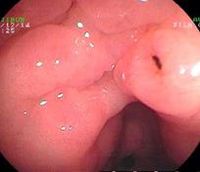

1.慢性浅表性胃炎又称慢性单纯性胃炎胃粘膜最常见的病变之一,中国国内胃镜检出率高达20%~40%,以胃窦部常见;胃镜见胃粘膜:胃粘膜充血、水肿,呈淡红色,可伴点状出血及糜烂,表面可有灰黄色或灰白色粘液渗出物覆盖;显微镜示:病变位于粘膜浅层; 2.慢性萎缩性胃炎根据发病是否与自身免疫有关及是否伴有恶性贫血,分为A、B型;A型属于自身免疫性疾病,患者抗壁细胞抗体(PCA)及抗内因子抗体(IFA)阳性,并伴有恶性贫血,病变主要位于胃体和胃底部;B型多见于胃窦部,无恶性贫血;两者胃粘膜改变相似;胃镜见胃粘膜:由正常的橘红色变为灰色或灰绿色,粘膜层变薄、皱襞变浅甚至消失、粘膜下血管透见,表面有细颗粒、偶见出血糜烂;显微镜可见淋巴细胞、浆细胞浸润、肠上皮化生、腺上皮化生、不典型增生;